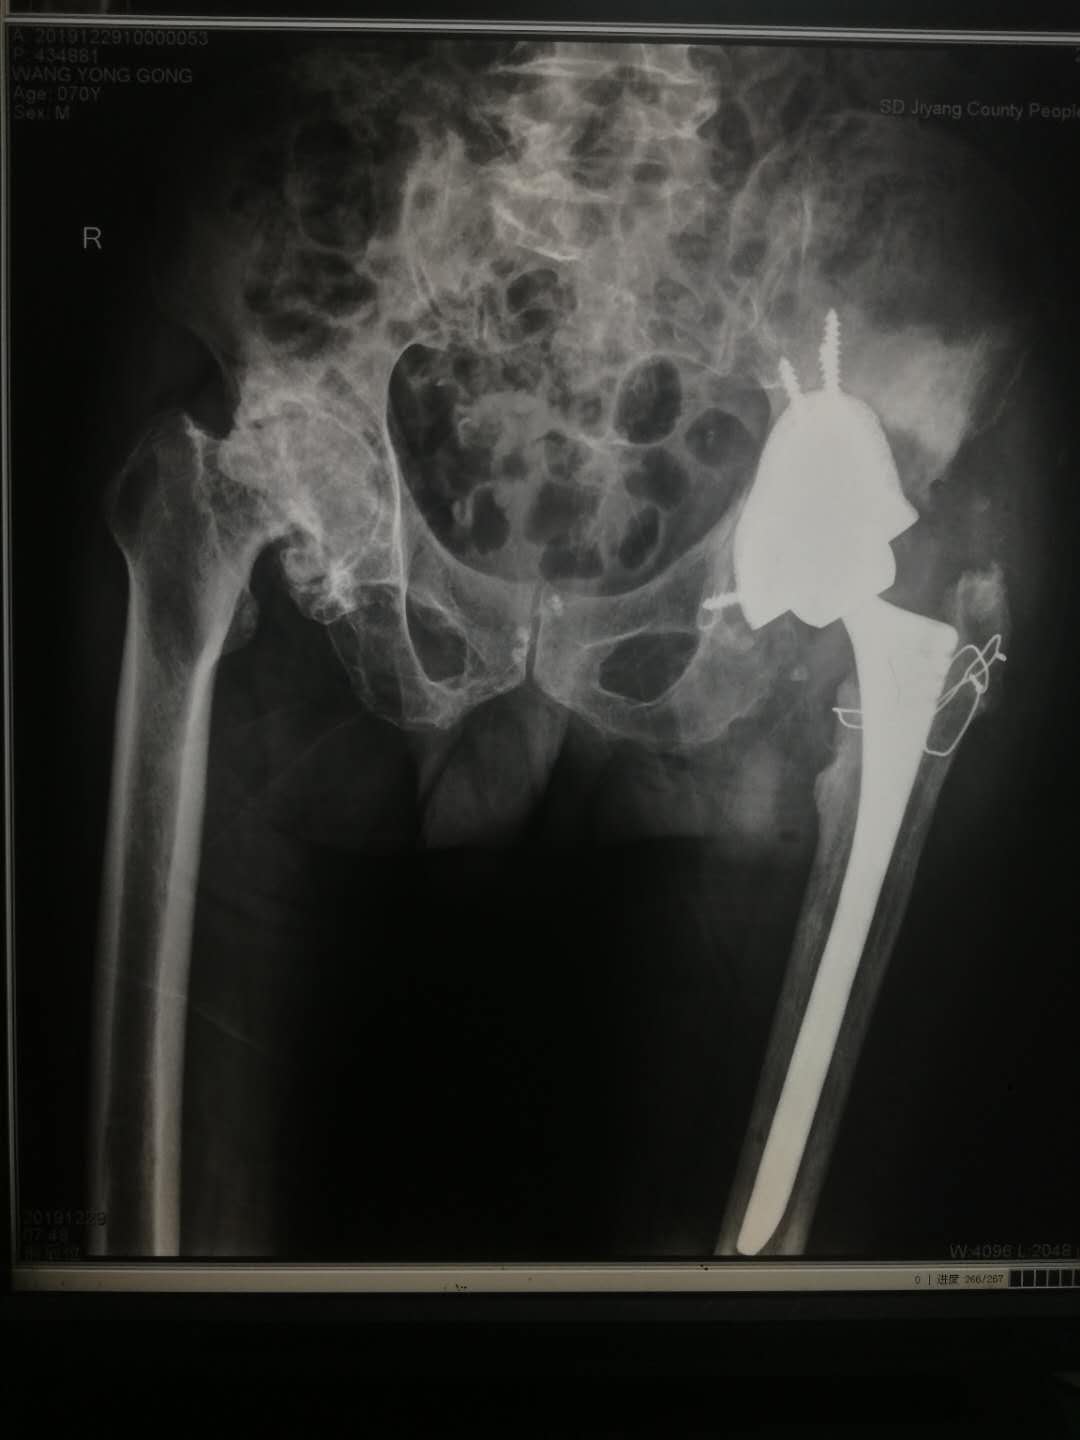

患者,王某某,男,70岁,6年前因股骨头坏死在区人民医院行人工全髋关节置换术,最近感髋部疼痛来院复查,拍片发现人工关节假体出现松动,髋臼假体已移位。入院后经CT等检查发现患者髋臼侧骨质有大量缺损,难以包容髋臼假体。董孟政主任医师组织全科进行会诊讨论,认为手术难度很大,请教省立医院骨科王先泉主任,决定采用3D打印技术辅助手术治疗。利用髋臼CT扫描的数据,用3D打印了机打印出一个与患者患病骨盆完全相同的骨盆模型,进一步确定骨缺损程度,再根据缺乏的部位、范围订制适合病人的异型髋臼假体。手术医师先在模型上模拟手术操作,经过反复计划模拟后 为病人实施了关节翻修术。手术顺利,术后病人很快恢复,随访时已能负重行走,对治疗效果满意。

此例3D打印技术的应用提高了手术质量,让治疗更加精准,明显缩短了病人的康复时间,使骨科医生对高难度关节翻修术增强了信心,标志着区人民医院的关节翻修技术水平再进一步。